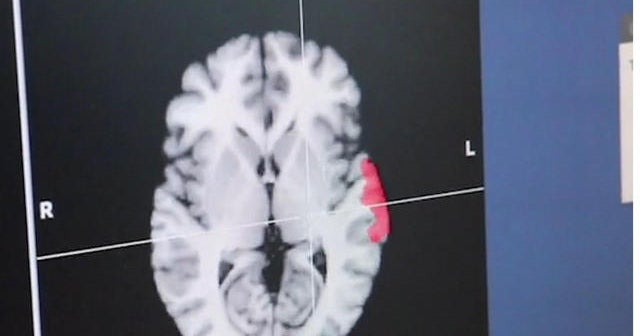

Siblings with autism have different genetic mutations

Typically, it's been thought that when two children from the same family have autism, it's a result of the same genetic mutations. A new study from Autism Speaks suggests that this isn't always the case; the genes that lead to autism are much more varied. Dr. Malika Marshall reports.